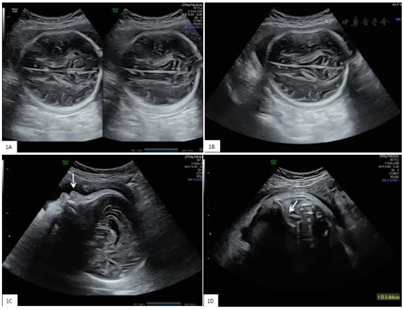

妊娠29周我院胎儿超声检查结果提示双顶径81 mm(+2.1 SD,按NICHD亚裔曲线计算,下同),头围279 mm(+1 SD),腹围274 mm(+2.6 SD),股骨长径48 mm(−2.5 SD),第六脑室存在宽约9.5 mm,胎儿头颅脑中线居中,颅内结构近场远场清晰度相似,近场颅骨光环受压变形,移开探头可恢复后(图1A、图1B)。鼻骨未显示(图1C)。胎儿羊水最大深度73 mm,指数203 mm,余胎儿结构未见异常。妊娠32周我院胎儿超声检查结果提示双顶径91 mm(+2.6 SD),头围310 mm(+1.6 SD),腹围317 mm(+3.2 SD),股骨长径58 mm(−0.6 SD),胎儿颅骨顶枕部膨隆,颅骨受压变形,近场颅内结构显示清晰,鼻骨未显示,右侧锁骨长3.84 mm(图1D),左侧锁骨未显示。

产前超声可以诊断CCD最早发表于1990年代中期[8,9]。产前超声主要征象是胎儿的颅骨骨化差,并伴有短锁骨或锁骨发育不全[10,11]。但这些研究均认为,由于锁骨发育不全的鉴别诊断包括许多骨骼发育不良,因此需要结合胎儿的其他骨骼发现来评估CCD。Soto等[12]研究采用3D超声产前诊断18周3 d的CCD胎儿主要超声表型为鼻骨缺失,并伴有颅骨低钙化。Hermann等[13]认为颅骨钙化不足及鼻骨缺失是CCD患者在出生前和出生后易于识别的特征,而且3D超声有利于识别这些超声影像。目前仅有少数散发CCD的产前超声报道。本文报道1例散发CCD的产前超声表现,主要表现为胎儿颅骨钙化差,顶枕部膨隆,颅骨受压变形,近场颅内结构显示清晰,鼻骨缺失,左侧锁骨不显示。引产后检查发现胎儿颅骨软,左侧锁骨未触及,遗憾的是孕妇拒绝尸检及放射性X线进一步检查。至于羊水过多是否是CCD产前超声的表型,目前尚未见报道,尚需更多的病例研究,但发现羊水过多时,超声检查时更应仔细,以免漏诊。也有文献报道,CCD患者可表现为腭盖高拱、不完全或完全性腭裂、下颌正中联合闭合延迟,这可能影响胎儿的吞咽功能。